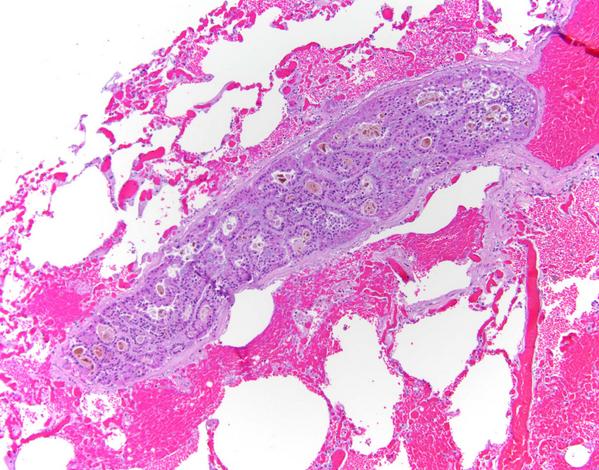

Image of the day: hepatocellular carcinoma metastasis to lung #pathologists #histology #forensic #pathology

http://t.co/eqg4xCOkLP